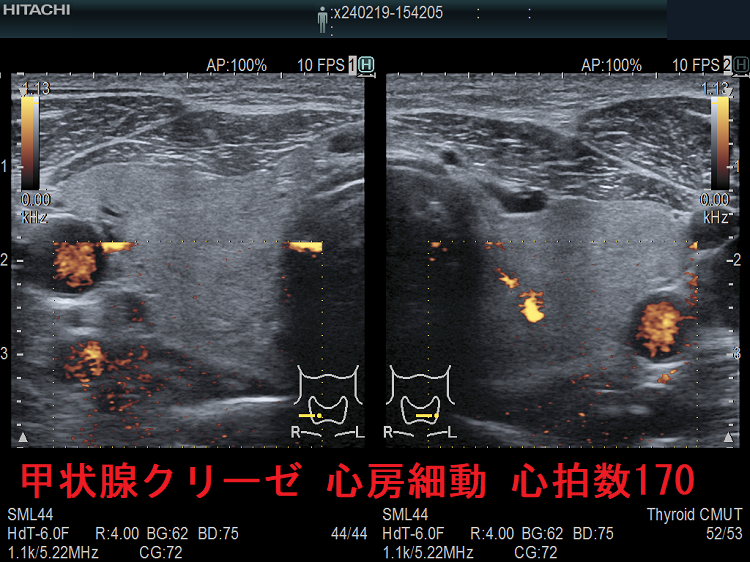

心房細動合併バセドウ病 ITA-PSV

下甲状腺動脈収縮期最大血流速度(ITA-PSV)測定にも欠点があります。

1. 心房細動(Af)合併の甲状腺機能亢進症/バセドウ病では、脈がバラバラなため、血流速度もバラバラになり測定不能です。

甲状腺クリーゼ 心房細動 心拍数170

甲状腺クリーゼ 心房細動(Af)を伴い心拍数170/分;心臓が空打ちをしているため内部血流はほぼゼロです。

甲状腺クリーゼ 心房細動 心拍数170 ITA-PSV

甲状腺クリーゼ 心房細動(Af)を伴い心拍数170/分 ITA-PSV;心臓が空打ちをしているため計測不能です。